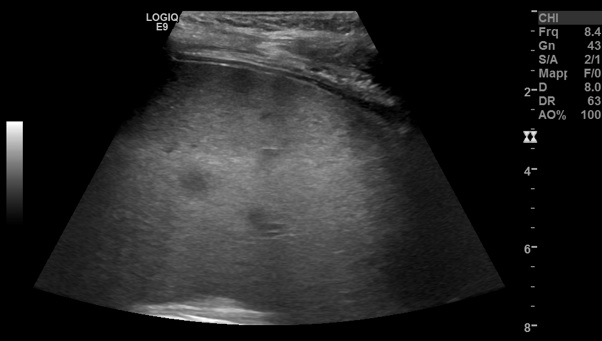

da possibili localizzazioni linfomatose. Figura 2. L�RMN

mostra numerose lesioni solide epatospleniche con intensa

ipervascolarizzazione in fase arteriosa a cercine di natura

infettiva. Figura 3. L�ecografia

lui, ma non ha linfonodi palpabili. Finalmente esegue la RMN (Figura 2) �lesioni solide epatospleniche con

intensa ipervascolarizzazione in fase arteriosa a cercine. Di natura

infiammatoria-infettiva

(lesioni granulomatose?)�